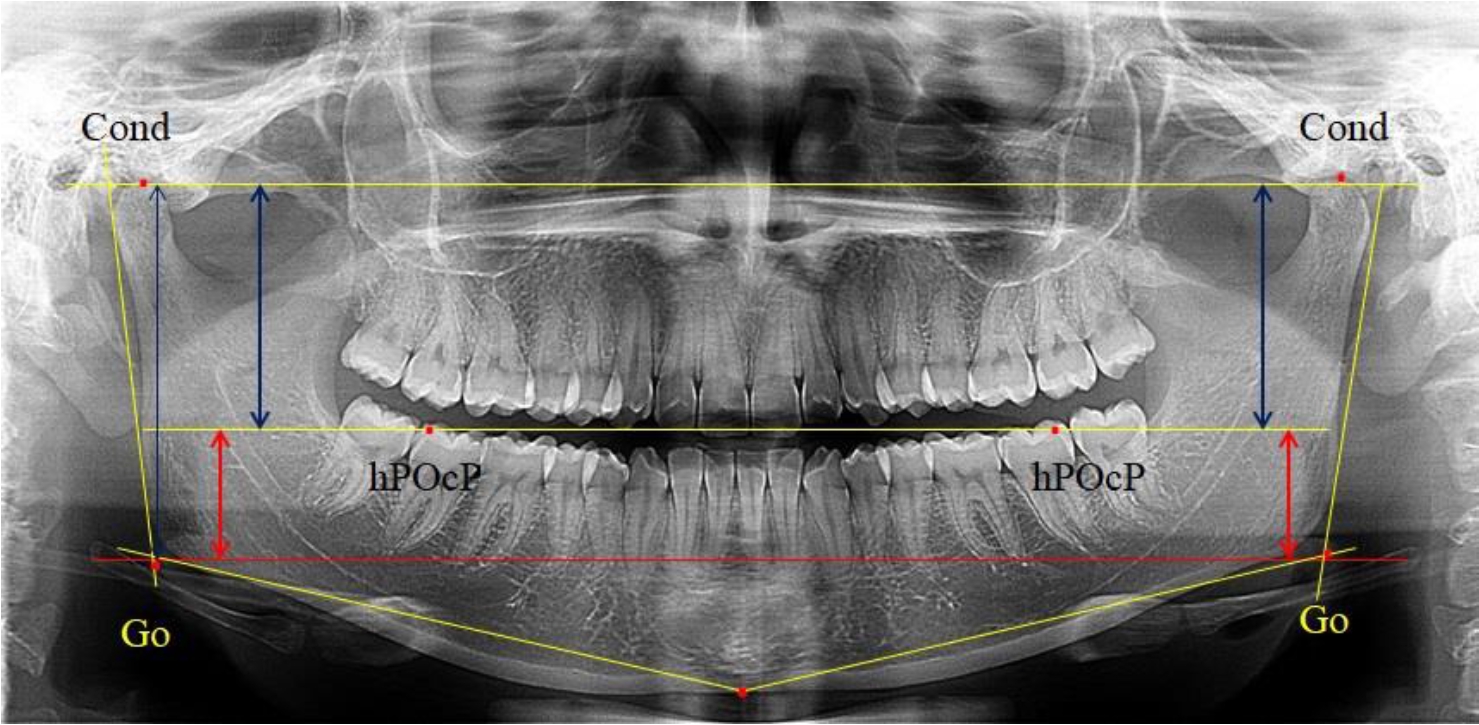

Во 2-ю подгруппу был включен 21 комплект телерентгенограмм и ортопантомограмм [или (28,38 ± 5,24) %], на которых средняя величина отношения верхней части ветви к нижней составляла 1,63 ± 0,03, что было достоверно меньше показателя, полученного по группе в среднем и в 1-й подгруппе.

Визуально параметры ветви отличались от первой группы (рис. 3).

Рис. 3. ОПТГ пациента 2-й группы с уменьшенным коэффициентом соотношения частей ветви нижней челюсти

Высота ветви составляла (62,75 ± 1,42) мм и достоверных различий по этому показателю не отмечено. Максимальная высота была 73 мм, а минимальная – 55 мм. Высота верхней части составляла (38,81 ± 0,76) мм, что было достоверно меньше, чем у людей 1-й подгруппы.

В то же время высота нижнего отдела ветви была (23,94 ± 0,73) мм, и показатель отличался в большую сторону по сравнению с аналогичным размеров в 1-й подгруппе.